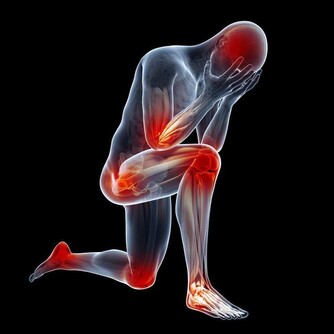

大量的生長激素會刺激骨關節異常增生,侵犯膝、踝、腕等大關節,出現腫脹、疼痛等症狀。

據報導,老年人肺癌合併關節痛的發生率約佔10%至20%。

因此,對中、老年人突然逐漸加重的肩臂痛,無論是否伴有呼吸道症狀,

且肩臂痛經牽引或止痛藥治療,只能暫時緩解症狀而不能阻止疼痛進行性加重時,就需高度警惕。